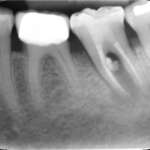

Le perforazioni iatrogene – Diagnosi e terapia

Iatrogenic root perforations. Diagnosis and therapy

Oggi grazie a nuovi materiali, strumenti e tecnologie, la prognosi delle perforazioni è notevolmente migliorata. Molti casi, che anni...